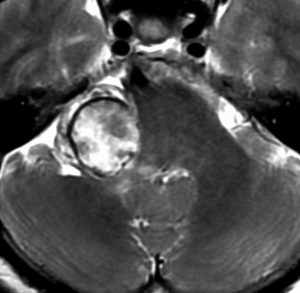

何も考えないで手術しなければならない時

聴神経腫瘍でまず手術が必要なのは巨大なものです。この4枚の写真は私が実際に手術をした患者さんのものです。脳幹部という脳の最も大切なところが腫瘍によって圧迫されて変形しているのが特徴です。右上のものはのう胞性腫瘍なので大きさの割に手術のリスクは高くありませんが,左上のものは実質性で出血性のものですごくリスクが高い手術でした。左下のものは普通のリスク。右下のものは超高難易度のものです。

この腫瘍は脳幹部変形がとても強く,大きいので手術摘出するしか選択肢はありません

- 脳幹部の変形が高度な大きな腫瘍になると手術するしかありません

- 4cmを超えると危険だと考えてください

- のう胞性(腫瘍の内部がほとんど液体)のものは4cmを超えても手術は危なくないです

- 巨大な充実性の聴神経腫瘍の手術では命をなくすリスクもあるものです

- 大きな腫瘍では無理して全部摘出せず,部分摘出術で小さくしておいてから,手術後に放射線治療をします